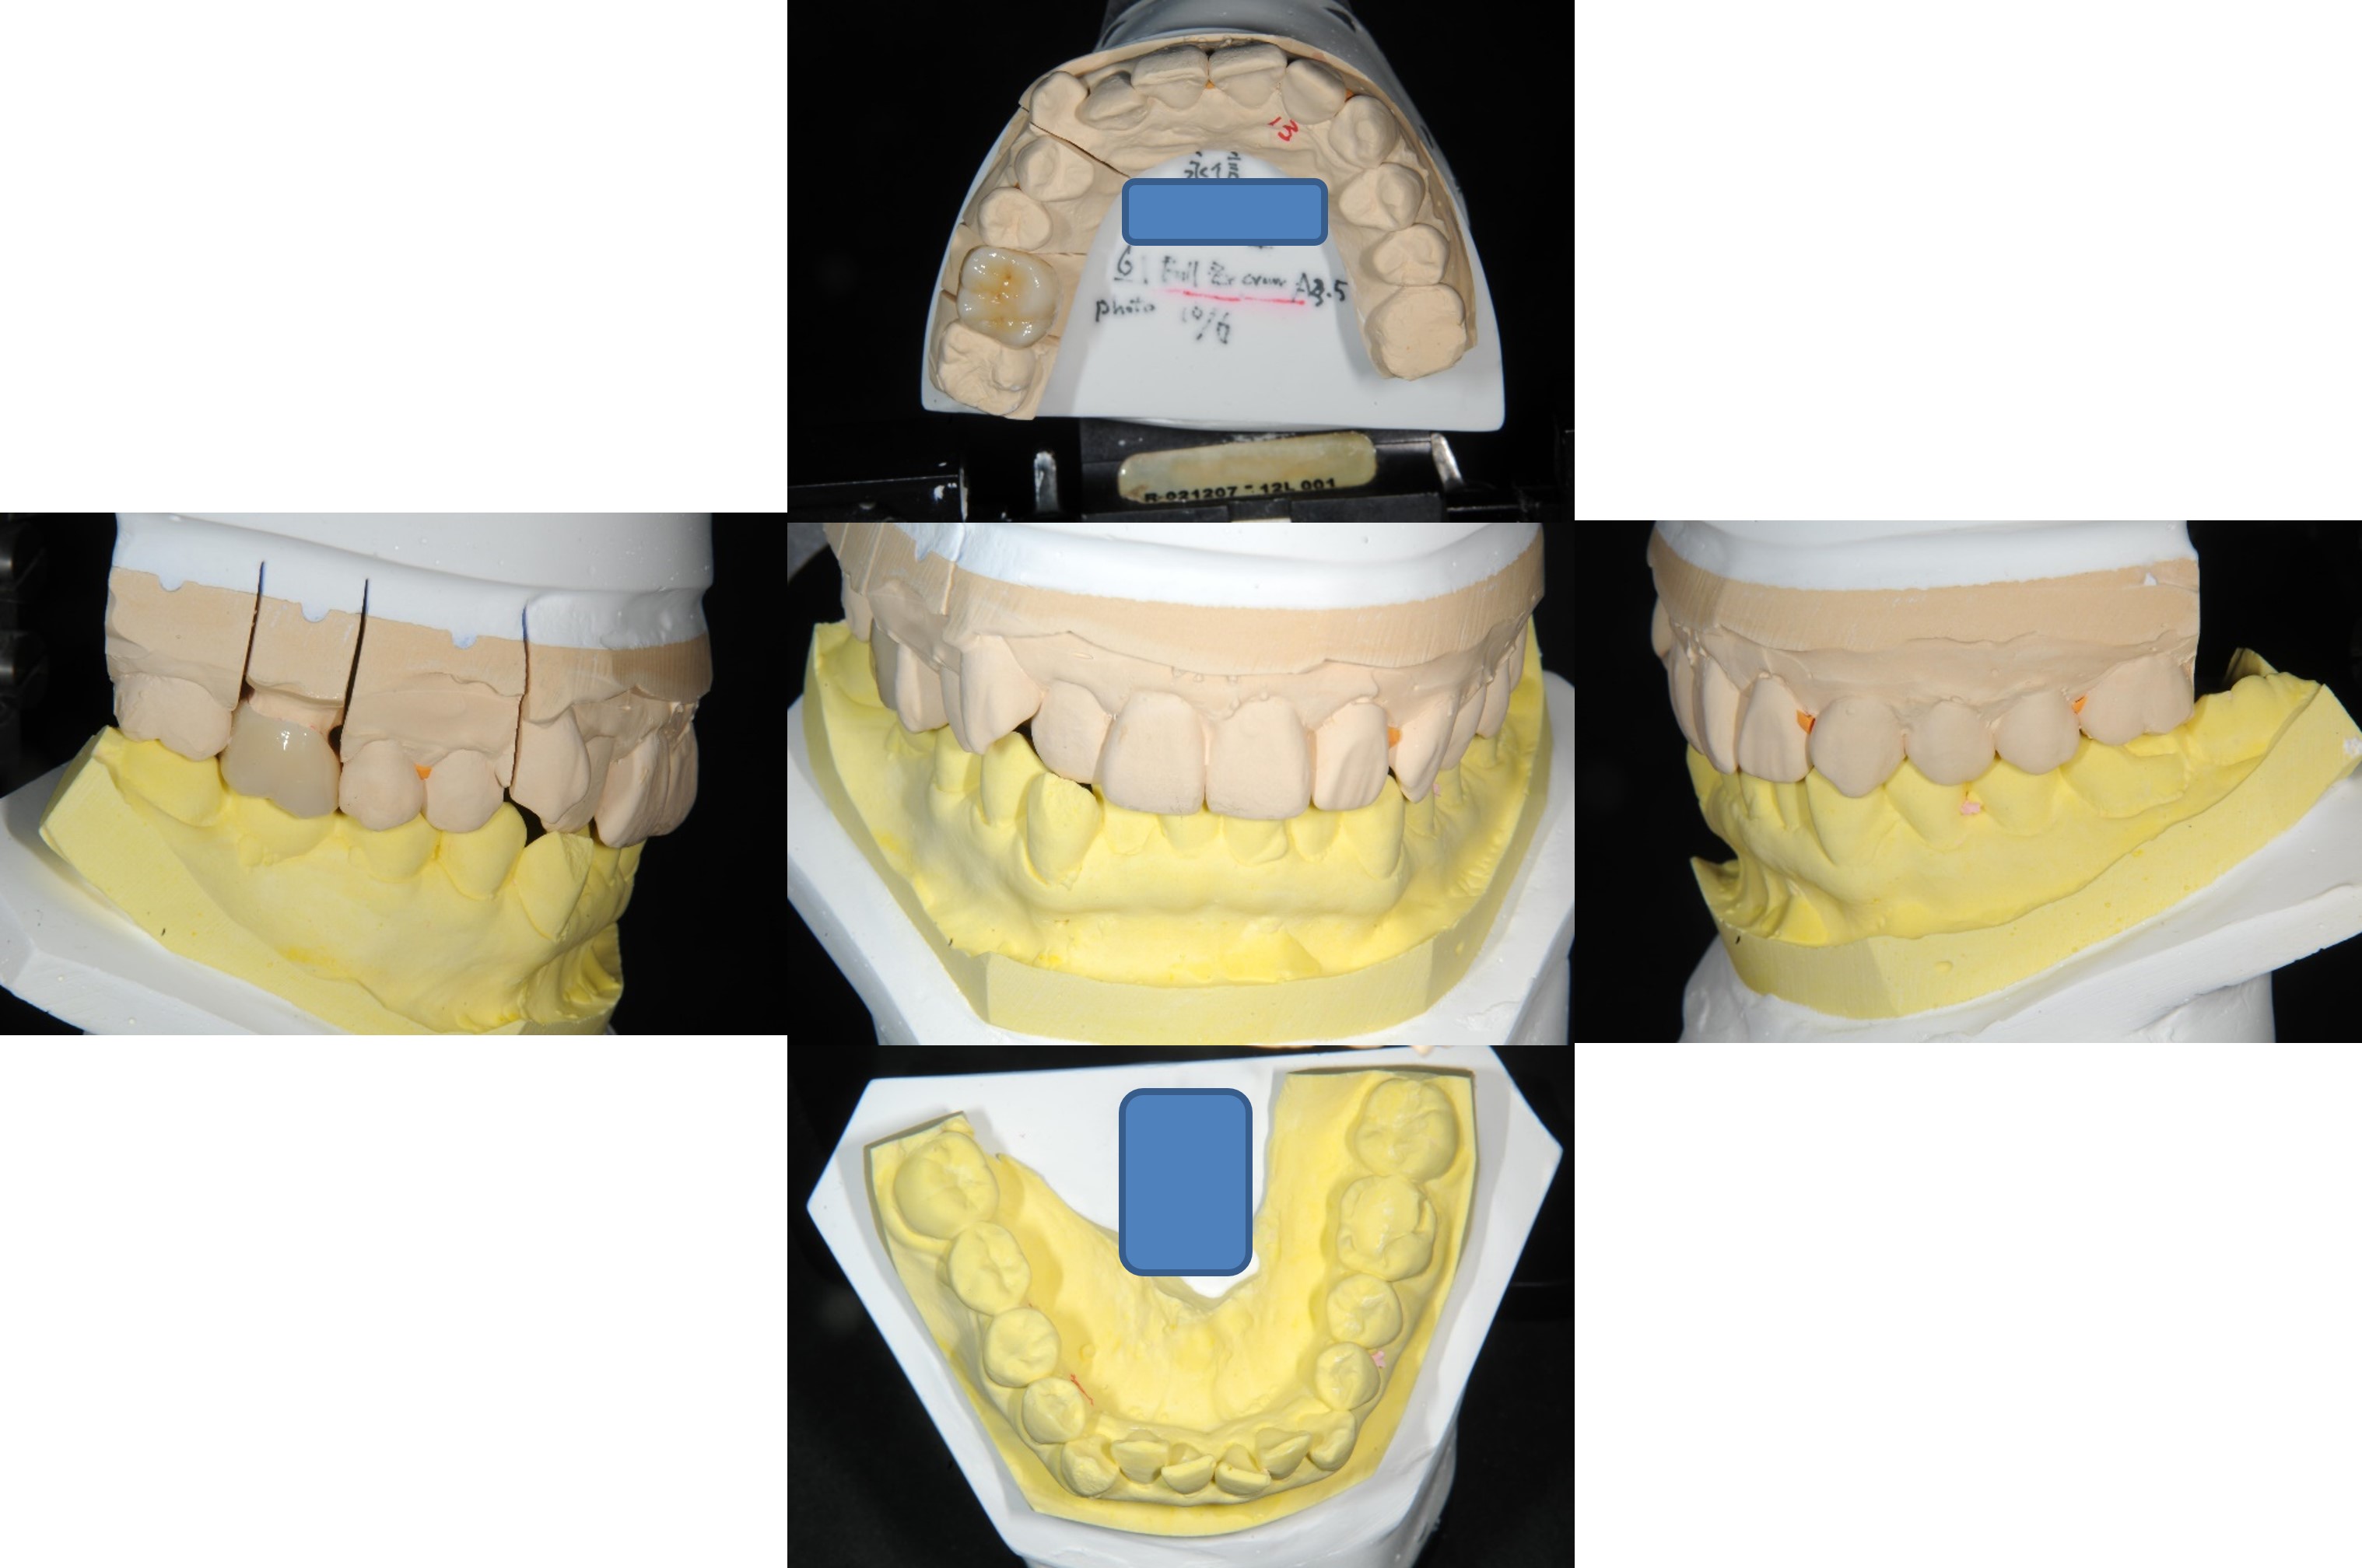

上面弓、上咬合器

技師於咬合器製作全瓷冠